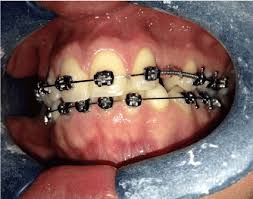

Natural autonomous eruption and forced eruption under orthodontic traction. Postoperative pain experienced by patients was similar, but regression of pain was faster in closed eruption technique. Forced eruption can preserve the natural root system and related periodontal architecture, resulting in years of additional service for the patient. It also can maintain adjacent tooth structure while retaining the option for future implant reconstruction. The postoperative recovery was longer after open eruption than close eruption technique (p = 0.000). 26,27 in the case shown here, closed eruption was chosen for the impacted central and. Dr vanarsdall recommends open exposure with a repositioned gingival flap (pediculated connective tissue graft) above the impacted canine. Management of unerupted maxillary incisors 6 5.4 incisor removal 5.5 ankylosed maxillary incisors.

This facilitates eruption and orthodontic traction. The difference in time required for the two techniques was statically significant (p = 0.000). 5.3.1 open exposure 5.3.2 closed eruption technique 5.3.3 open versus closed eruption techniques. Patients perception of recovery after exposure of impacted teeth: If a canine is associated with severe resorption of the root of the incisor, an open exposure is not indicated since it endangers the vitality and existence of the incisor. If the crown is positioned mesial to the lateral incisor, a closed technique for the pataltal eruption of canine. Two techniques for exposing palatal canines are routinely used in the uk: The mean surgical time table 3 for open eruption technique was 22.31 ± 1.98 min as compared to 30.87 ± 2.38 min to closed eruption technique.

Patients perception of recovery after exposure of impacted teeth: The difference in time required for the two techniques was statically significant (p = 0.000). The closed technique and the open technique. This facilitates eruption and orthodontic traction. Closed eruption technique for surgical exposure 3 surgical approach can be used 1. The postoperative recovery was longer after open eruption than close eruption technique (p = 0.000). It also can maintain adjacent tooth structure while retaining the option for future implant reconstruction. (1) window technique, (2) full flap open procedure, and (3) apically repositioned flap technique.